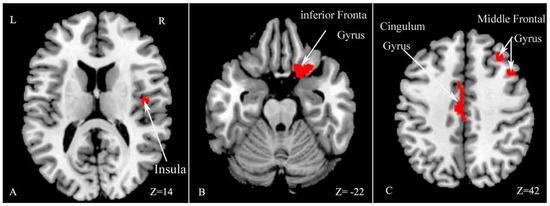

VBM analysis revealed GM volume decreases in several regions in MS patients compared with HCs, including the right insula, middle frontal gyrus, inferior frontal gyrus and left cingulate gyrus (p < 0.05, family-wise error (FWE) corrected for multiple comparisons, see Table 2 and Figure 2).

Figure 2.

Statistical parametric mapping (SPM) regions with decreased gray matter (GM) volume in patients compared with healthy controls (p < 0.05, family-wise error (FWE) corrected for multiple comparisons). SPM regions exhibiting significant GM loss: right insula (A); right inferior frontal gyrus (B); right middle frontal gyrus and left cingulate gyrus (C). R: right; L: left.

The current study revealed several main findings. First, MS patients exhibited worse performance on the SDMT and PASAT-3″ compared with HCs. We found extensive WM damage, including cortical and subcortical GM atrophy in the right insula, middle frontal gyrus, inferior frontal gyrus and left cingulate gyrus in MS patients compared with HCs. In addition, CI–MS patients exhibited worse performance on the Auditory Verbal Learning Test (AVLT), Verbal Fluency Test (VFT), PASAT-3″, Brief Visuospatial Memory Test (BVMT), and Trail making test (TMT) compared with CP–MS patients. CI–MS patients showed a widespread reduction in FA values in many WM tracts throughout the skeletons, compared with CP–MS patients. The results also revealed regional GM atrophy in several regions, including the right temporal lobe, left insula and bilateral caudate.

The current results revealed a significant difference in SDMT and PASAT-3″ performance between MS and HC, which primarily reflects information processing speed and working memory performance. This finding is consistent with previous reports [1,16]. Moreover, we found widespread WM impairment, as well as cortical and subcortical GM loss in a number of areas, including the insula, frontal gyrus and cingulate gyrus, in accord with a number of previous studies [10,11,12,17,18,19,20]. Both WM and GM abnormities are known to be involved in MS.